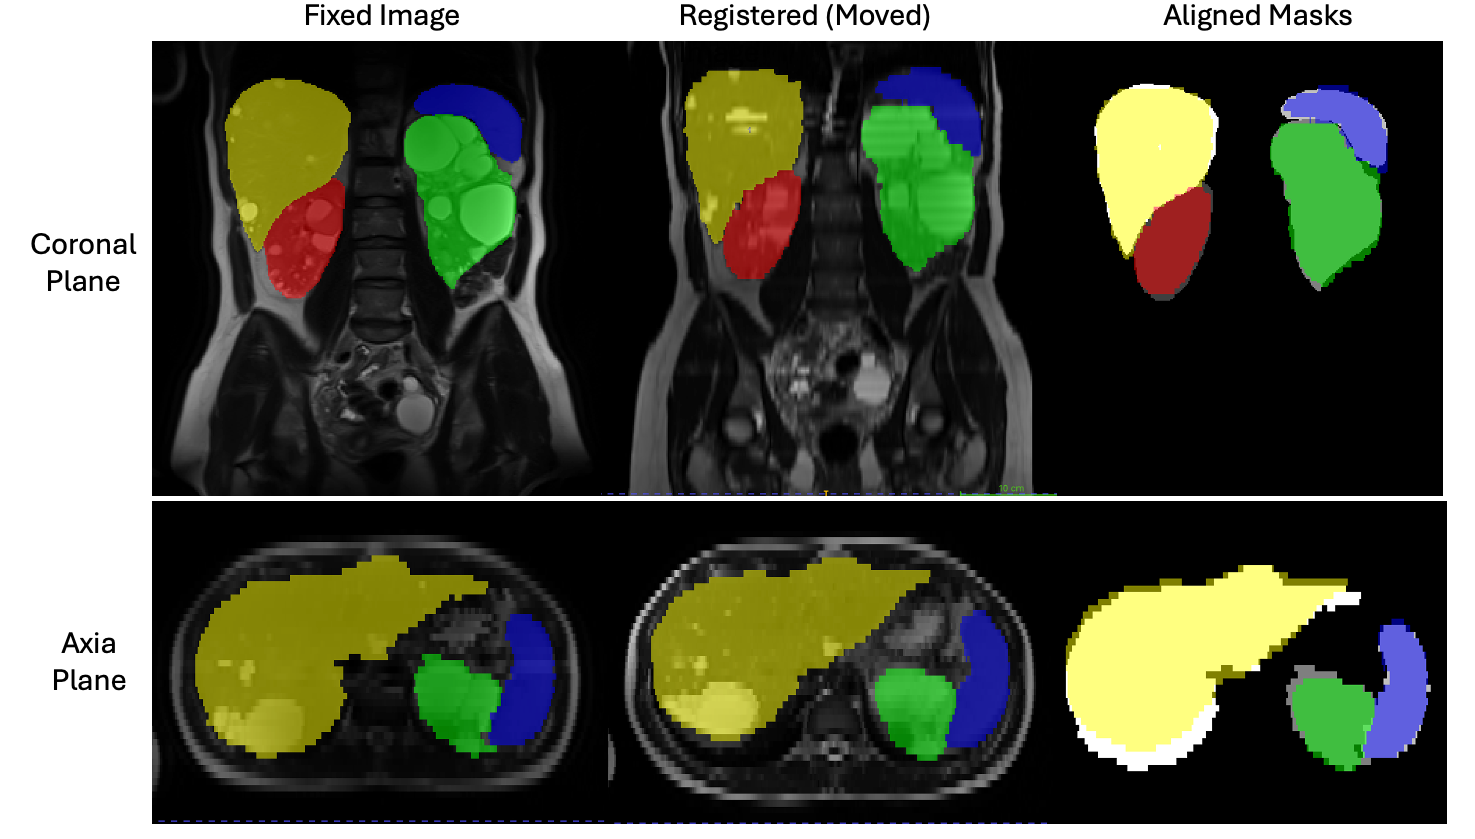

Fig. 4 illustrates a registration example of a moving image in axial plane to the fixed image in coronal plane, along with their segmentation masks. The right column shows the overlap between the segmentation masks after registration. Our results shows that, on average, across patients, RKM achieves the following median (IQR) Dice scores of 82% (6%),—83% (6%), 70% (14%), and 80% (6%), for Right Kidney, Left Kidney, Spleen, and Liver, respectively.

Figure 4: Fixed and moved image as well as their mask alignments for representative slices in axial and coronal views from a sample patient in the test set. Red: Right Kidney, Green: Left Kidney, Yellow: Liver, and Blue: Pancreas.